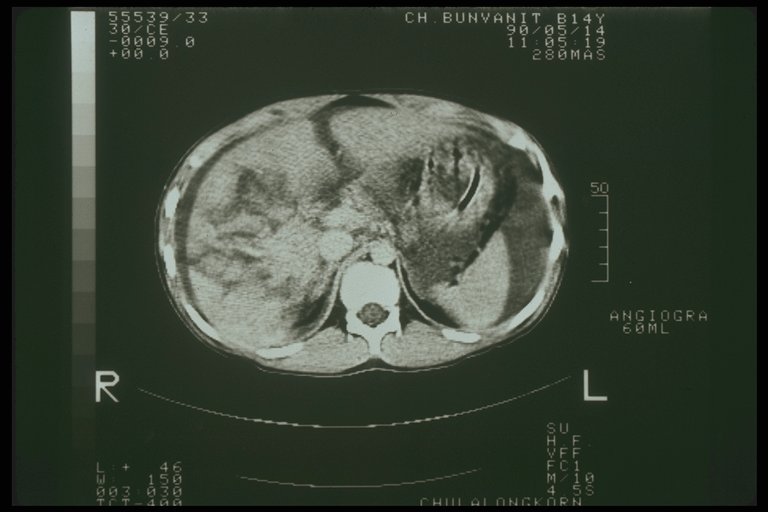

Splenic laceration demonstrated by CT scan

Combined severe liver injury and splenic hematoma, intraperitoneal bleeding is also noted